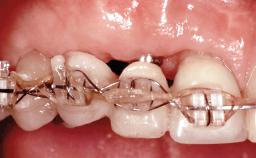

Replacement of Four Incisors with a Fixed Partial Denture on Two Narrow-Neck Implants after Implant Failure

| Loading Protocol | Conventional or early |

| Retention | Screw-retained, with splinted implants Screw-retained, with splinted implants |

| Interim Prosthesis during Healing | Removable Removable |